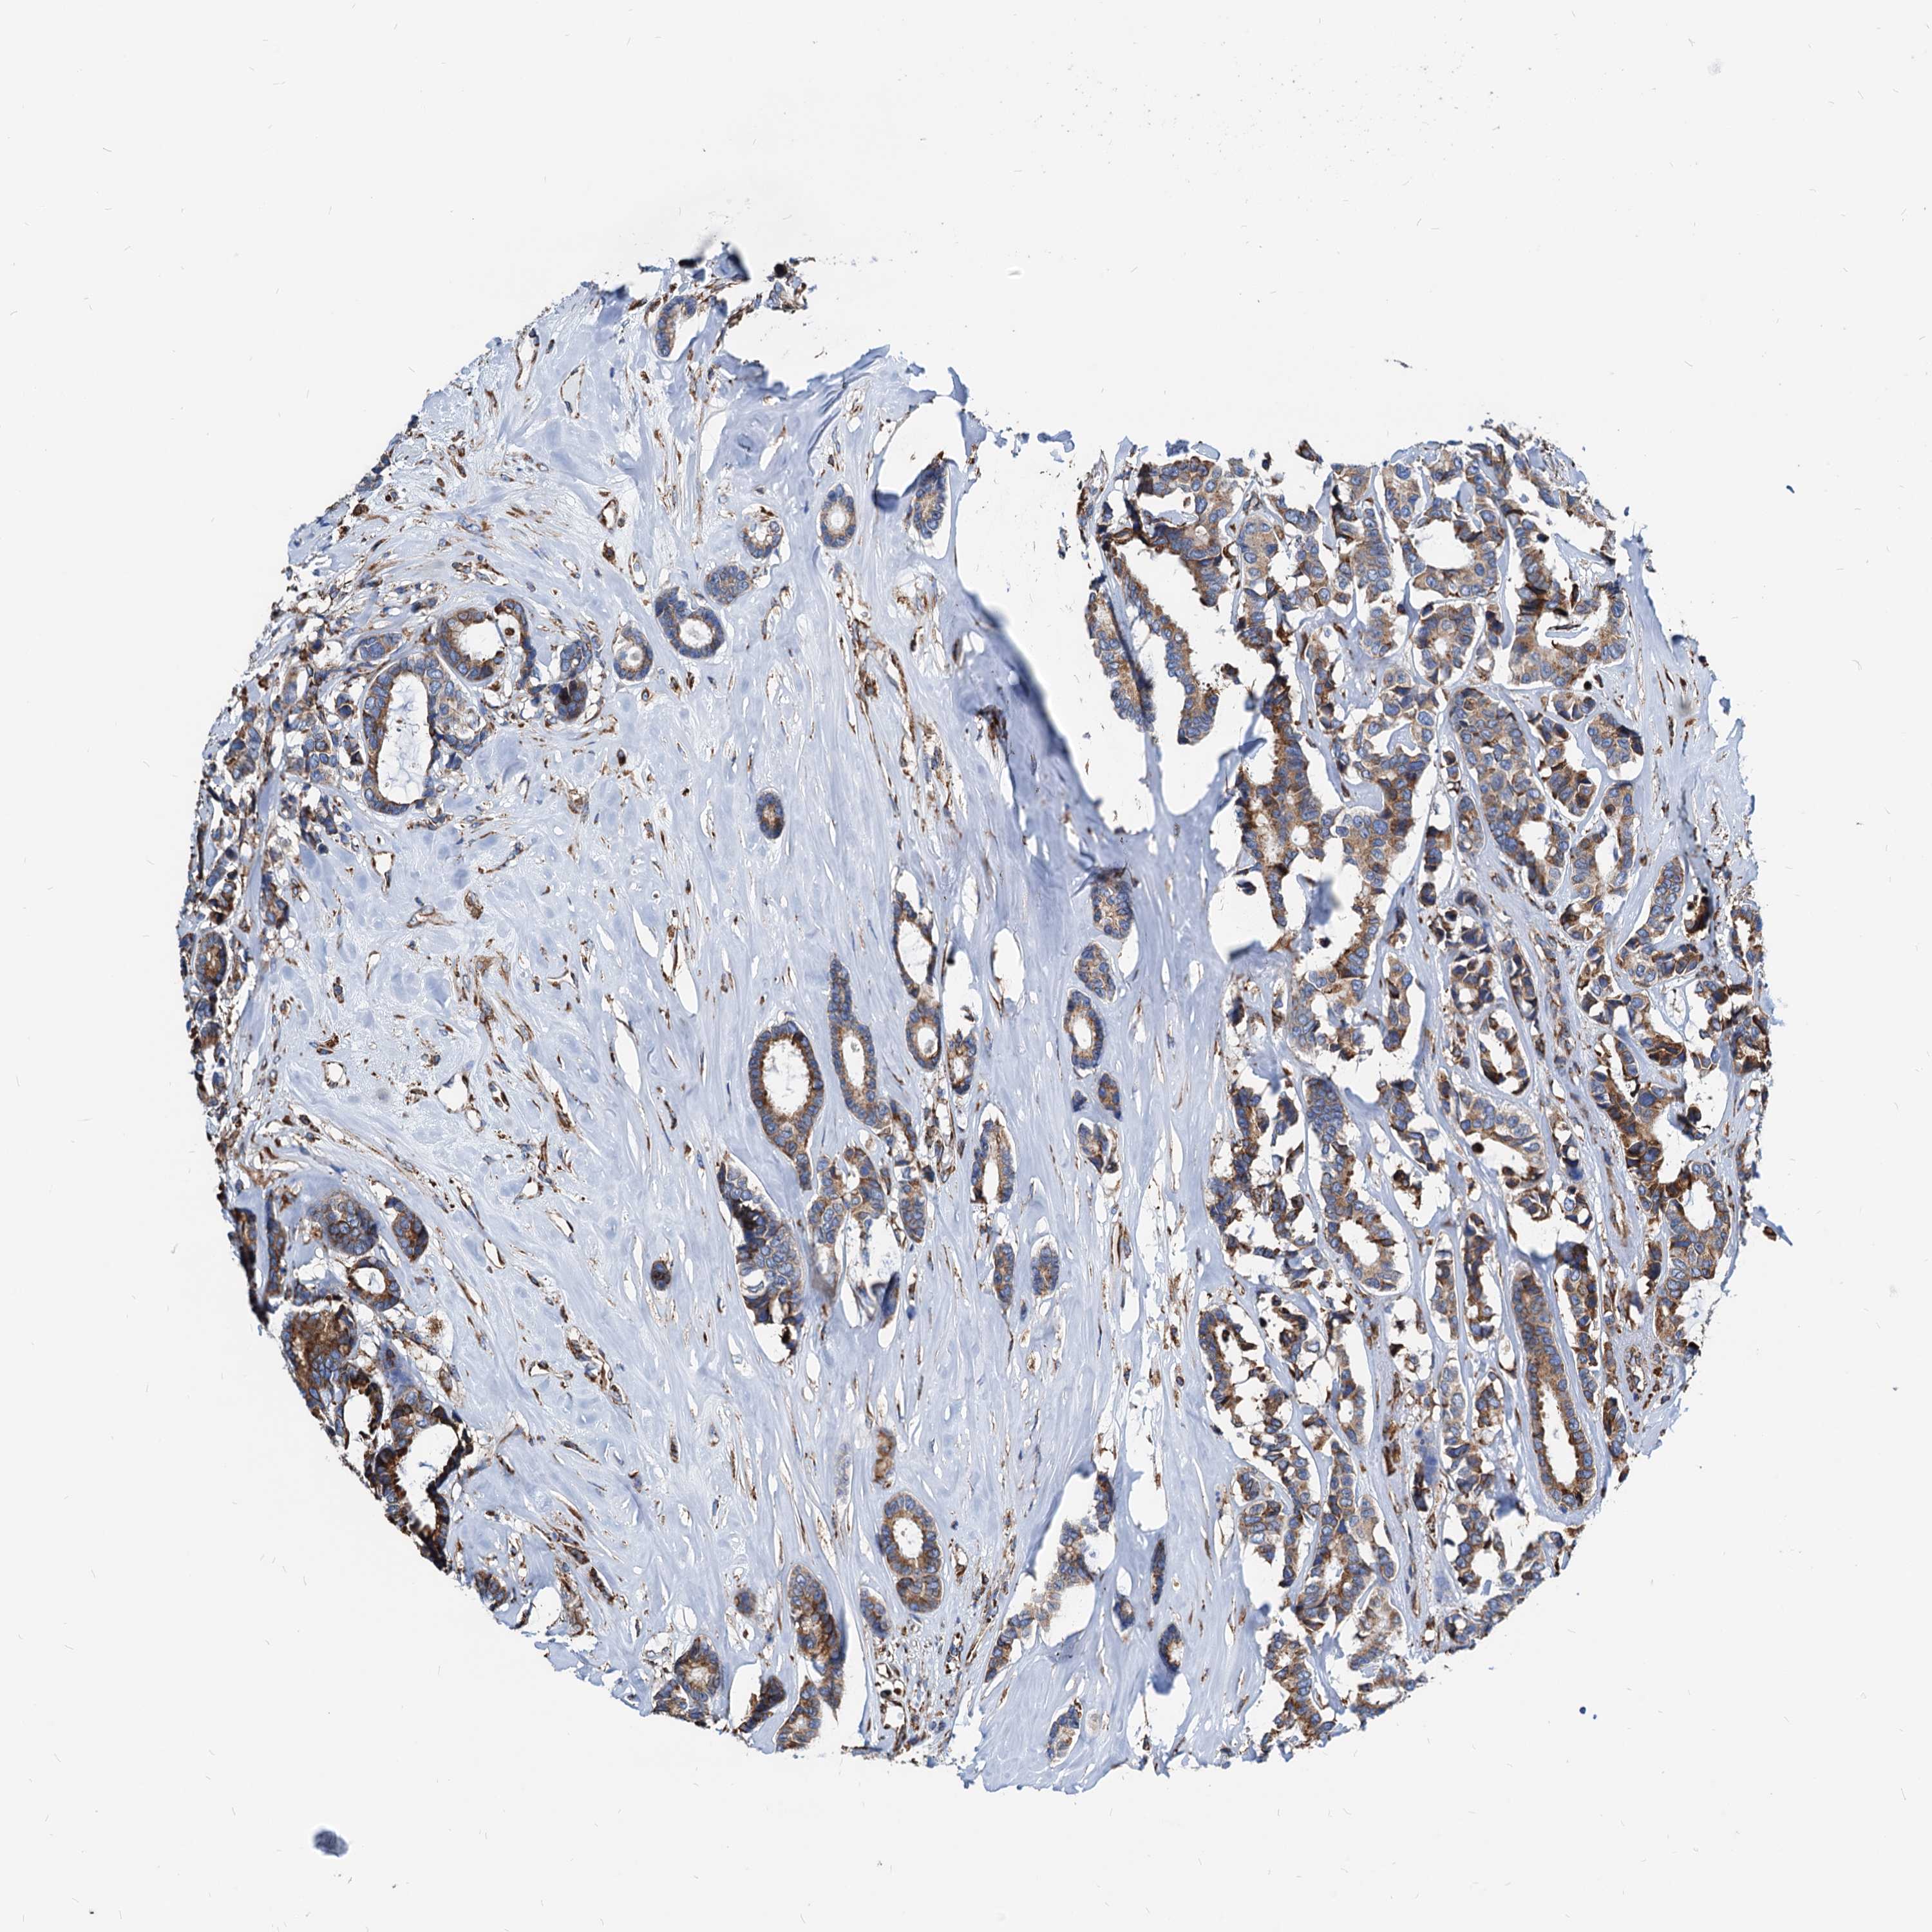

CANCER BREAST CANCER Show tissue menu

BRCA TCGA BRCA VALIDATION PROTEIN EXPRESSION

ANTIBODIES

AND

VALIDATION